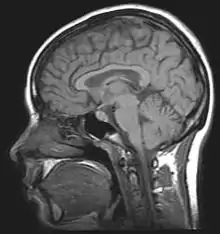

The leading experimental technique for studying proactive interference in the brain is the “recent-probes” task. Initially, this is when participants must commit a set of items to memory. They then ask them to recall a specific item. Assessing them is shown by a probe.[10] Thus, using recent-probes task and fMRIs, the brain mechanisms involved in resolving proactive interference identify as the ventrolateral prefrontal cortex and the left anterior prefrontal cortex.[11]

Brain structures

Retroactive Interference has been localized to the left anterior ventral prefrontal cortex by magnetoencephalography (MEG) studies investigating Retroactive Interference and working memory in elderly adults.[23] The study found that adults 55–67 years of age showed less magnetic activity in their prefrontal cortices than the control group. Executive control mechanisms are located in the frontal cortex and deficits in working memory show changes in the functioning of this brain area.[23]